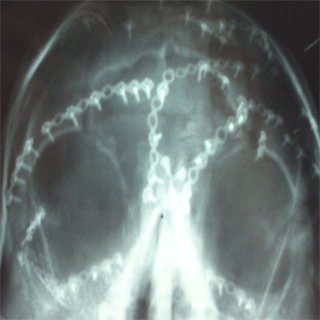

X-rays and post-op pictures

A closer shot of the platework aaround the bridge of my

nose, eye sockets and forehead.